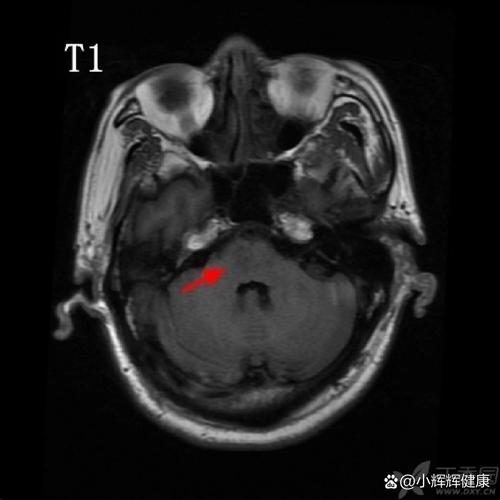

- 脑梗死:通常指“缺血性脑卒中”,即由于脑部血管堵塞(如血栓形成或栓子脱落),导致局部脑组织因缺血缺氧而发生坏死。

脑桥梗死的危害性极大,因为它直接损害了这个“生命中枢”的核心区域,其危害程度和具体表现,取决于梗死灶的大小、位置以及是否影响到关键的神经结构。

(图片来源网络,侵删)